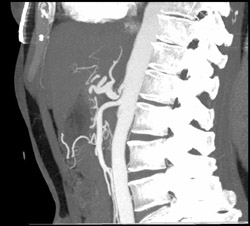

Splenic Artery Aneurysm